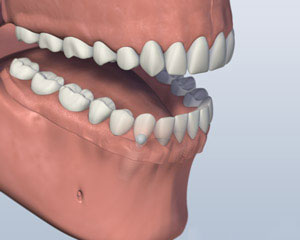

3. 义齿附

3. 义齿附

3. 义齿附

3. 修复完成